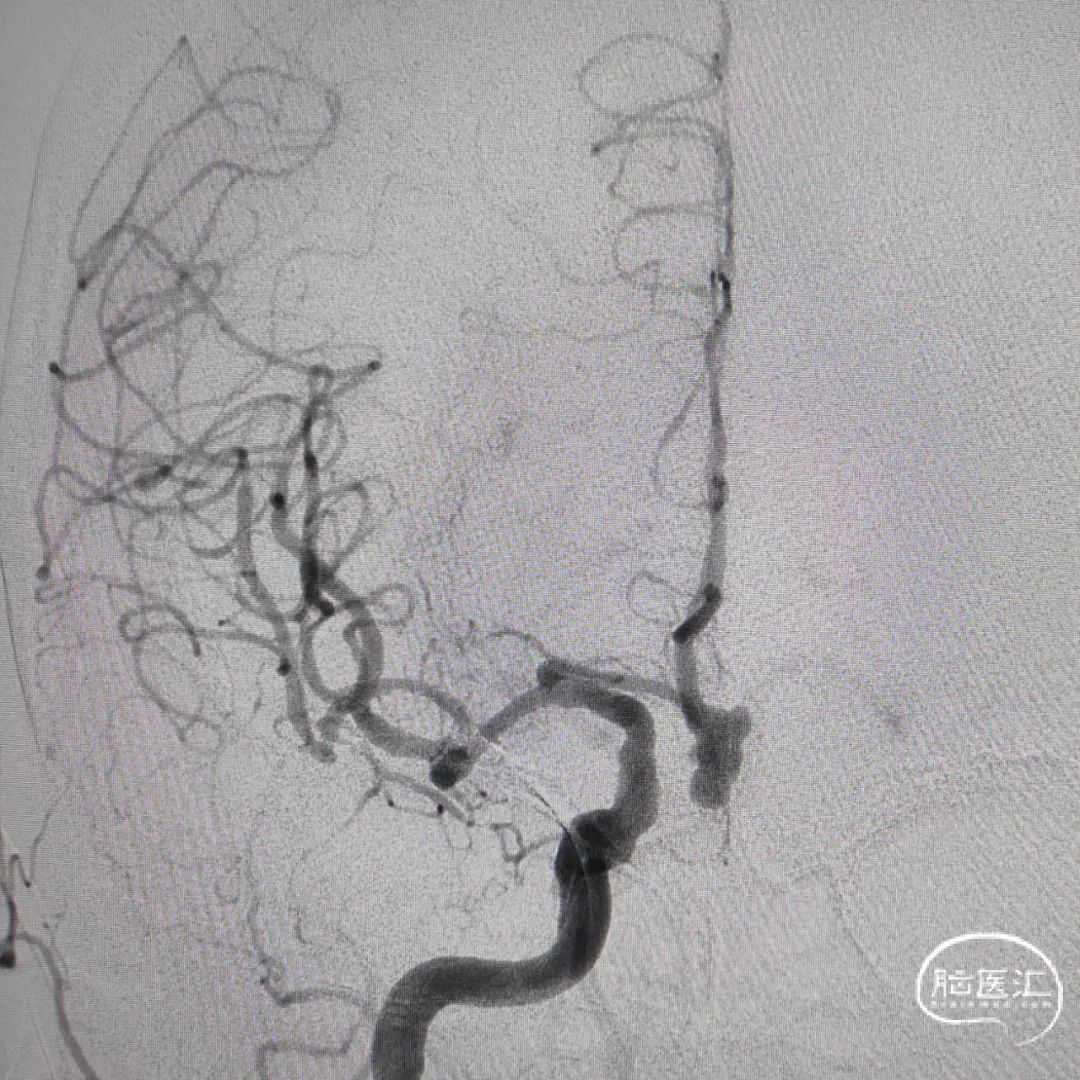

脑血管造影及3D重建示前交通动脉瘤,大小约7.6*5.2*4.8mm,瘤颈宽3.8mm,3个子瘤分别朝向不同方向,瘤颈处子瘤朝向对侧上方,考虑为动脉瘤破裂处。